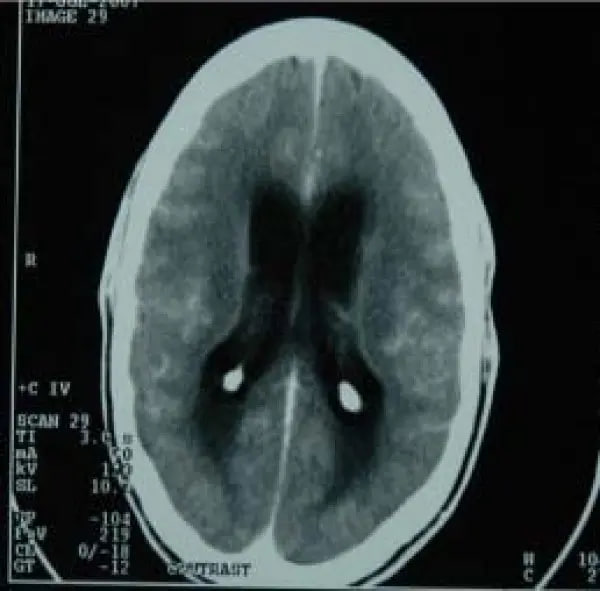

Це клінічна форма туберкульозу, при якій відбувається специфічне запальне ураження центральної нервової системи. При цьому виникає інфікування мозкових оболонок туберкульозною мікобактерією з розвитком серозного менінгіту з переважним ураженням основи головного мозку.

На відміну від багатьох інших випадків бактеріального менінгіту, туберкульозний часто важко діагностувати, адже початкові клінічні прояви, як правило, є підгострими й часто неспецифічними, а менінгеальні симптоми, як правило, не виявляються на ранній стадії захворювання. Через пізню діагностику ефективність його лікування вкрай низька, часто туберкульозний менінгіт закінчується летальними випадками.